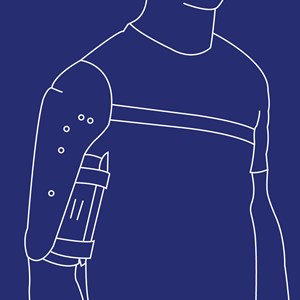

Overarmsortose (BO–Brachial Ortose)